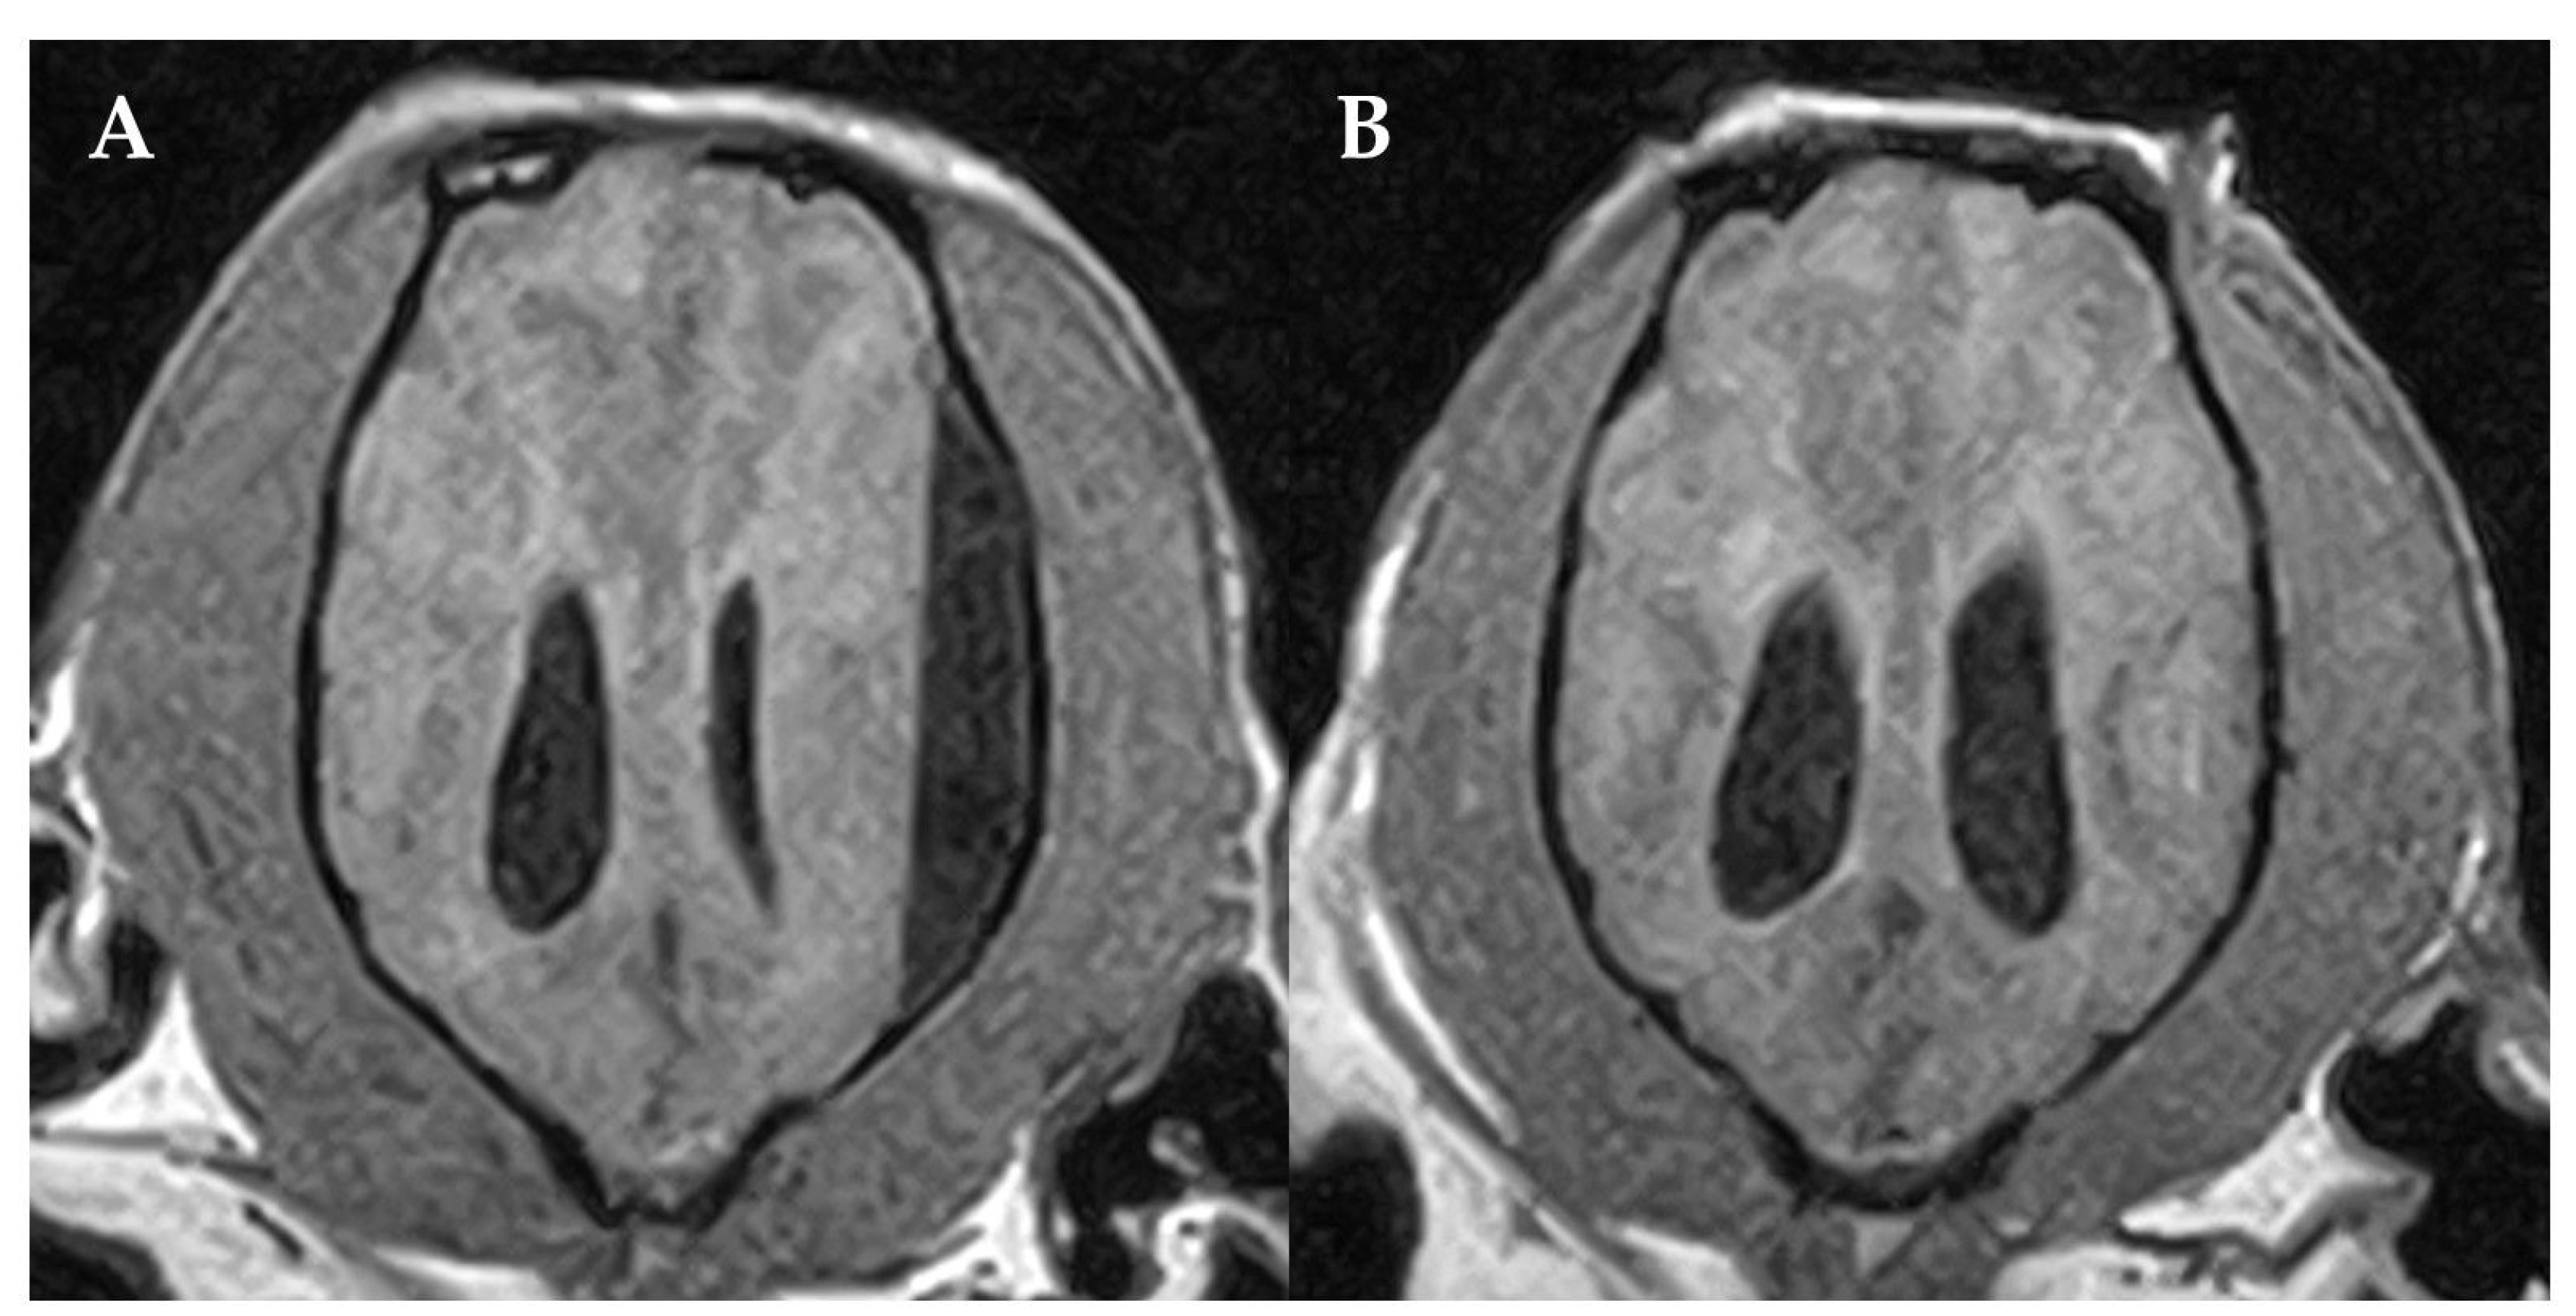

Figure 3.

Pre- (A) and post-surgical (B) MRI of the dog´s brain. Dorsal 3DT1W (A,B). Post-surgical MRI (B) confirmed the resolution of the SFA. The left side of the patient is on the right side of the image.